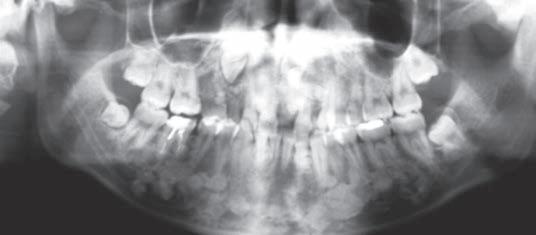

A 16-year old male patient presents to your clinic with a desire to remove his wisdom teeth. He reports having some dental work done in the past and that he has “something in his jaws” that his previous dentist discussed with him but has no other medical history to report. You take the following panoramic radiograph.

What disease or pathology do you suspect?

A) Multifocal Idiopathic Osteosclerosis

B) Florid Cemento-Osseous Dysplasia

C) Multiple Osteomas Associated with Gardner Syndrome

D) Intramedullary Osteosarcoma

(continued on page 22)

Pathology Puzzler (continued from page 11)

Gardner Syndrome is a rare inherited disorder characterized primarily by its multiple colorectal polyps and propensity to develop colorectal carcinoma. Multiple benign tumors are also associated with Gardner syndrome, as are several maxillofacial manifestations. Among them are multiple gnathic osteomas and multiple supernumerary teeth, often causing impactions.

The genetic driver of Gardner syndrome is mutation in the APC gene, located on chromosome 5. This gene is a tumor suppressor gene that regulates cell growth and prevents cell from dividing when normally functioning. Gardner syndrome is an autosomal dominant disease with 100% penetrance, and often patients have at least one parent who are also affected. However, one-third of cases seem to be related to novel mutations.

In the present case, multiple radiopacities representing osteomas are seen throughout the mandible and maxilla. These range in size dramatically, but lack any associated radiolucency. Multiple impacted teeth can be seen, and astute diagnosticians may spot supernumerary teeth. This combination of signs points towards Gardner Syndrome.

The implications of a diagnosis of Gardner syndrome significantly include the risk of developing colorectal carcinoma. By age 30, half of patients will develop colorectal carcinoma. The lifetime risk of developing colorectal carcinoma approaches 100% in these patients. Recognition of the maxillofacial findings can allow for prompt referral and preventative therapies.

Multifocal idiopathic osteosclerosis is a diagnosis of exclusion- particularly as idiopathic osteosclerosis is much more commonly unifocal. All other possible etiologies and causes should be ruled out before idiopathic osteosclerosis is diagnosed clinically. Idiopathic osteosclerosis should not be associated with multiple supernumerary teeth.

Florid cemento-osseous dysplasia is a disease process better characterized radiographically as a mixed radiopaque and radiolucent process. Advanced lesions can be completely calcified, but that does not make it a good fit for the radiograph in this case. As a benign fibro-osseous lesion, this entity is important to recognize and diagnose to avoid unnecessary bone manipulation which can possibly result in osteonecrosis. It is uncommon to see this entity affect the inferior border of the mandible as was seen in the present case.

Intramedullary osteosarcoma would present with a moth-eaten radiolucency showing cortical and medullary destruction, possibly with the classic periosteal reaction “Codman’s Triangle” and blastic lesion in a “sunburst” pattern. In the present case, no bone destruction is noted.

Bryan Trump, DDS, MS Carter Bruett, DDS, MS